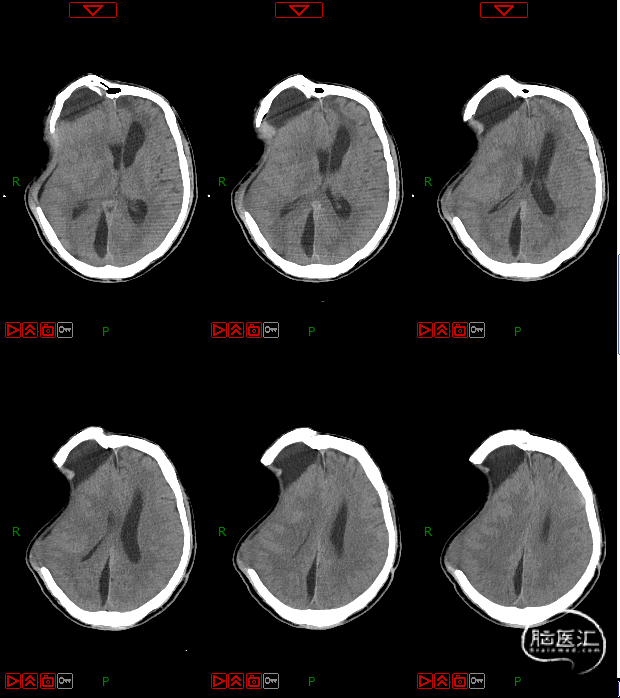

4. 动态复查头部CT

8月21日复查CT:硬膜下积液增加,脑室扩张明显,间质性水肿加重;对患者治疗方案进行调整,转神经外科治疗。

脑积水的处置